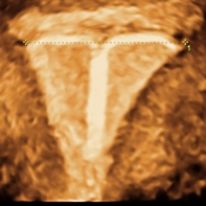

IUDs that fit properly have the least risk to cause side effects. Both the TCu380A IUD (Paragard®), left, and the Mirena® LNG-IUS have a transverse arm length of 32 mm. If the uterine cavity is wide enough, the risk of pain, bleeding expulsion and embedment is low.